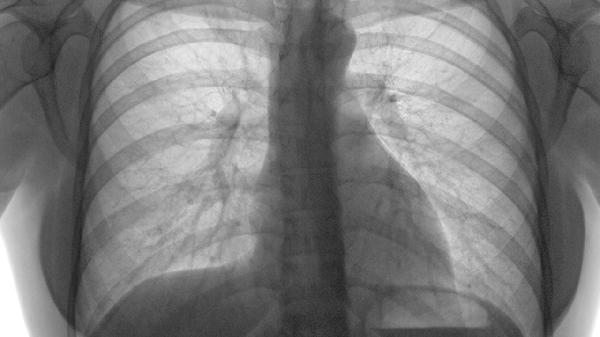

发生肋骨骨折伴开放性气胸时,禁止自行处理伤口或服用止痛药物。应保持患者安静,避免剧烈咳嗽或深呼吸。转运过程中需密切观察呼吸、脉搏变化,采取半卧位减轻呼吸困难。康复期需加强营养支持,适量补充优质蛋白如鱼肉、鸡蛋等,促进骨折愈合。定期复查胸片评估肺复张情况,在医生指导下进行呼吸功能锻炼。